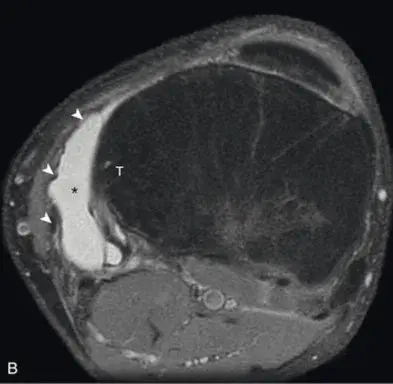

Киста Бейкера на МРТ

Диагностируют кисту Бейкера при помощи клинического осмотра пациента, УЗИ исследования коленного сустава. Киста подколенной ямки хорошо видна на МРТ. Показана рентгенография сустава для обзорной оценки соотношений бедренной и большеберцовой костей, хрящей и мягких околосуставных тканей. Рентген позволяет исключить возможные сопутствующие заболевания (артроз, опухоли сустава, процессы обменного характера и др.). Важным сегментом диагностики являются лабораторные исследования для выявления причины воспаления капсулы сустава.

Киста Бейкера – непростое заболевание. Оно требует выверенных подходов к диагностике и лечению. Для диагностики используют специальное оборудования и соответствующие технологи: УЗИ диагностика, рентген колена, МРТ коленного сустава.